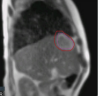

Unity enables the delivery of the radiation dose while simultaneously visualizing the tumor and surrounding healthy tissue with high-quality MR images. The system also integrates advanced tools that allow clinicians to adapt the patient’s treatment to this current anatomical information within a treatment session.